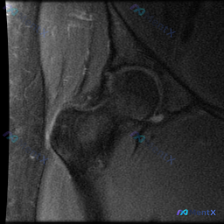

看到一份髋关节MRI T1序列冠状位的病例材料,用户预设想了解盂唇病变的可能性。 先看基础影像分析: - 扫描范围:单侧髋关节区域,包括股骨头、股骨颈、大转子、髋臼及其关节间隙 - T1序列特征:正常骨髓高信号,皮质骨低信号,肌肉中等信号,关节软骨及韧带清晰 - 股骨头/股骨颈:轮廓光滑,未见水肿、...

看到一个髋关节MRI病例,先给大家分享一下核心发现: 影像类型:髋关节MRI冠状位T1加权成像 主要表现:股骨头及股骨颈近端骨髓呈弥漫性T1低信号,与正常脂肪骨髓的高信号形成鲜明对比;髋臼顶轮廓清晰,关节间隙无明显狭窄,盂唇在T1序列上未见明确撕裂征象。 患者主诉提到了“盂唇病变”,但影像核心是骨髓...

整理到一个髋关节MRI分析的内容,仅提供了单张T1序列冠状位图像,临床关注点是盂唇病变。先看一下这张图像的客观描述: 骨骼结构:股骨头圆形,轮廓光整,骨皮质连续,骨髓信号均匀;髋臼形态连续,骨皮质清晰;大转子区域骨皮质完整。 关节间隙:宽度基本对称,无明显狭窄,无异常信号填充。 软骨与盂唇:股骨头表...

整理到一张髋关节T1加权冠状位MRI的病例资料,初始有人提问「能否观察到盂唇病变」。先放这张图的核心影像描述:图像聚焦一侧髋关节,股骨头形态基本呈圆形,股骨头前上方负重区皮质下可见清晰带状低信号影,其余股骨头、颈骨髓信号为正常脂肪高信号,关节囊无明显增厚或积液。 想问问大家:仅看这张图的描述,您第一...